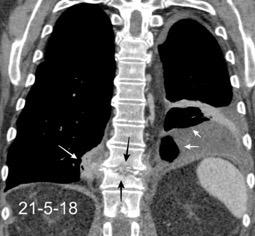

Marzo 2014: Perforación longitudinal distal secundaria a episodio de vómito (síndrome de Boerhaave). Derrame pleural izdo. que evoluciona a empiema.

Wang C-T et al. Tension hydropneumothorax in a Boerhaave syndrome patient: A case report . World J Emerg Med, 2021. Katabathina V et al. Nonvascular, nontraumatic mediastinal emergencies in adults:a comprehensive review of imaging findings. Radiographics. 2011.